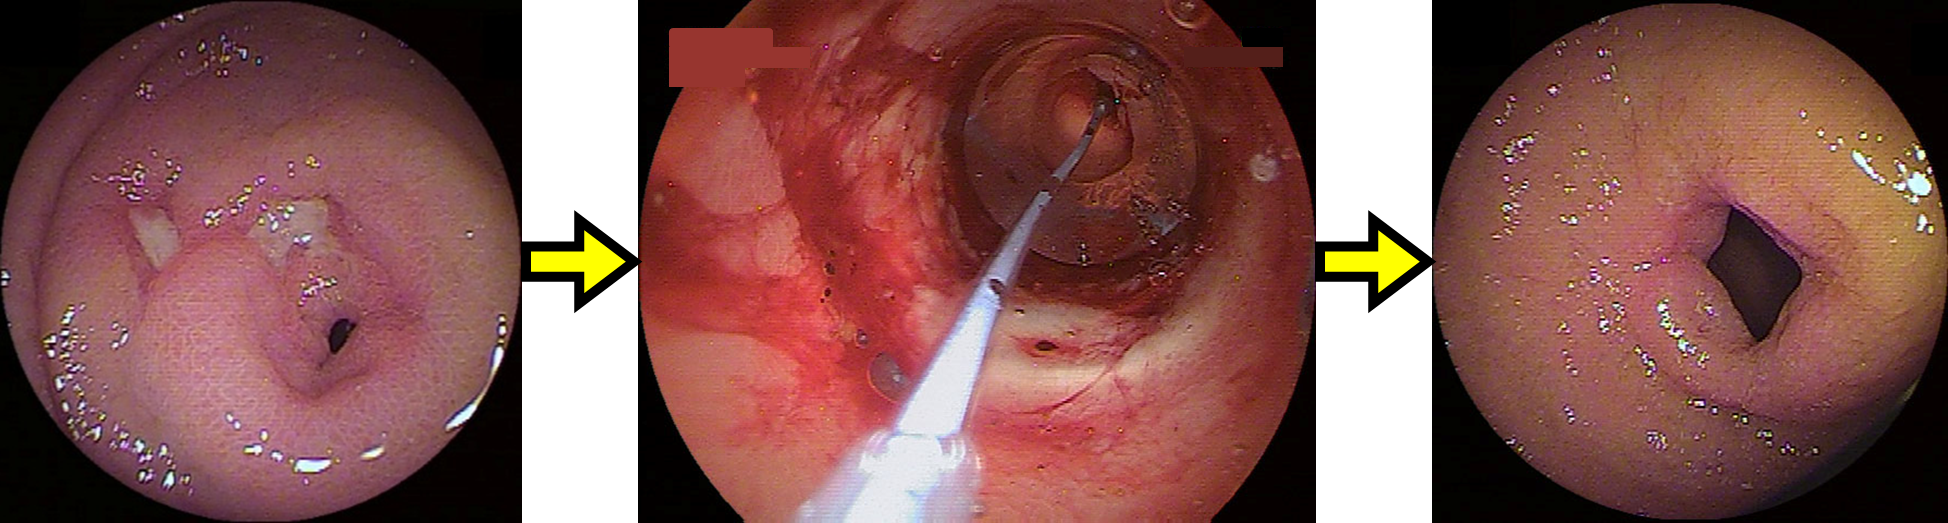

腸管が狭窄した場合は(特に小腸狭窄)、本院と連携し、バルーン内視鏡を用いてバルーン拡張術を積極的に行い、外科手術をなるべく回避できるように工夫しています。

しかし、内視鏡的に拡張が困難な場合や腸閉塞に至った場合は、信頼できる外科医と連携し、最小限の手術で、腸管の機能を少しでも温存できるような手術を行います。術後は再手術を回避できるよう内科治療の強化や見直しを行っています。そのほか穿孔・瘻孔、腹腔内の膿瘍などの合併症が発生した際にも外科治療が必要となります。